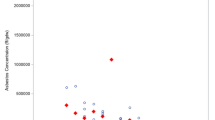

All the fibres identified corresponded to amphiboles (crocidolite 45%, anthophyllite 22%, tremolite 16%, amosite 15% and actinolite 3%). In 14 patients (37%), a single type of asbestos was found in the lungs (amosite in two, actinolite in one, anthophyllite in four, crocidolite in five and tremolite in two). Forty-six percent of the AF analysed had a length > 5 µm and a diameter < 0.2 µm.